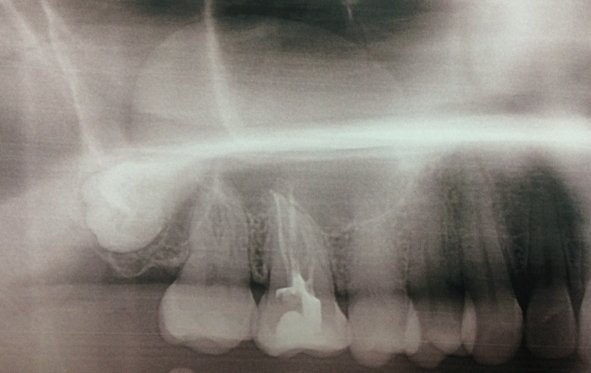

Здравствуйте! Есть ли у меня киста? Если да, то как срочно нужно делать операцию и как она называется?

Какой зуб вы имеете ввиду? Уточните. 18 и 48 зуб необходимо удалить. Далее расскажу после уточнения.